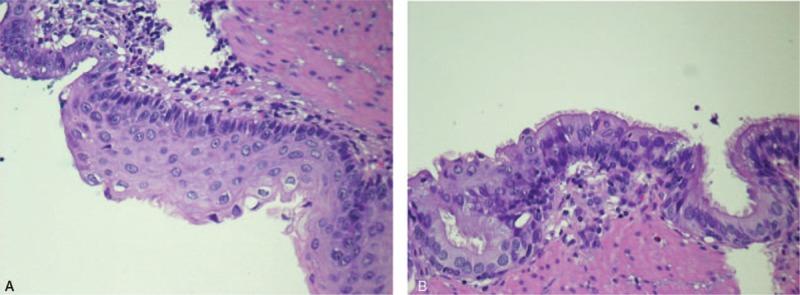

Post-operative pathological report confirmed the diagnosis of esophageal duplication cyst.

术后病理报告证实为食管重复囊肿。